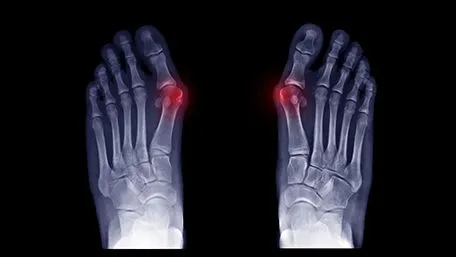

• bunions—also known as hallux valgus, these are joint enlargements that occur at the base of the big toe due to improperly fitted shoes or heels

Regular foot checkups with your podiatrist can prevent the formation of the toe joint and nerve disorders. Prevention of toe joint disorders is key to keeping your feet healthy. Your podiatric physician will conduct a thorough foot exam to examine your feet, as well as resthe types of footwear you most often wear, as well as your lifestyle. X-rays, as well as other imaging tests, can help determine the presence of bone spurs, as well as any toe joint disorders.